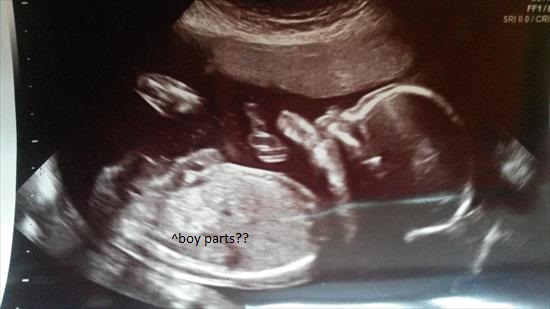

Hi, I had my 20 week scan last week at 19+6 and have only now noticed after looking at this pic what looks like boy parts? It's the white shape above the writing, any ideas? Thank you!

I hope not! The penis would be inside the belly.

Lol, thanks for replying, that's what my mum said but I've never seen this 'shape' on an ultrasound before.